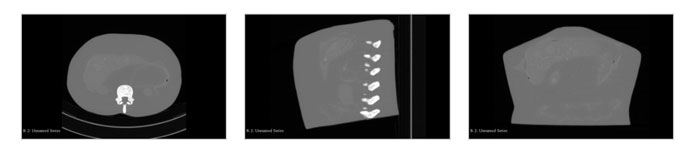

US-A03腹部模體,US-A03 FAST模體,US-A03成人腹部模型CT掃描成像圖: